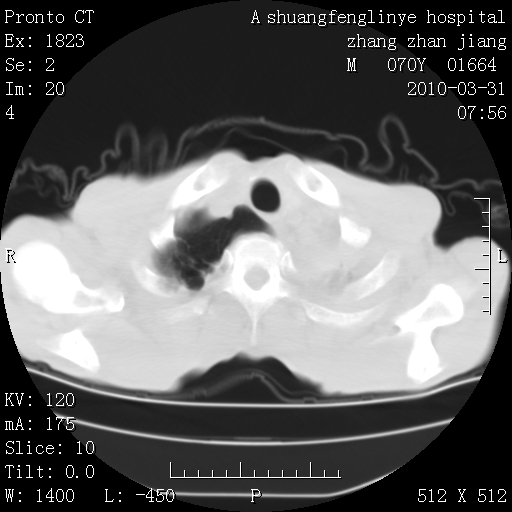

标题: CT25450:肺结核?

支持,不过左肺中叶那个像陈旧病变的结节要不要单报一下,在图上没看到钙化单报一下放心啊

双上肺继发型tb并左上空洞形成,主动脉冠脉钙化。

支持:继发性肺结核伴空洞形成!建议纤支镜检查待出外周围型肺癌可能!

1)两肺上叶继发性肺结核并左肺上叶空洞形成。2)冠状动脉及主动脉钙化。